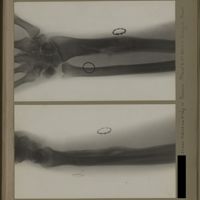

0137 - Page 25 - [Radiographies de l'avant-bras]0137 - Page 25 - [Radiographies de l'avant-bras]

0140 - Page 28 - [Radiographies de l'avant-bras]0140 - Page 28 - [Radiographies de l'avant-bras]

0143 - Page 31 - [Radiographies de l'avant-bras]0143 - Page 31 - [Radiographies de l'avant-bras]